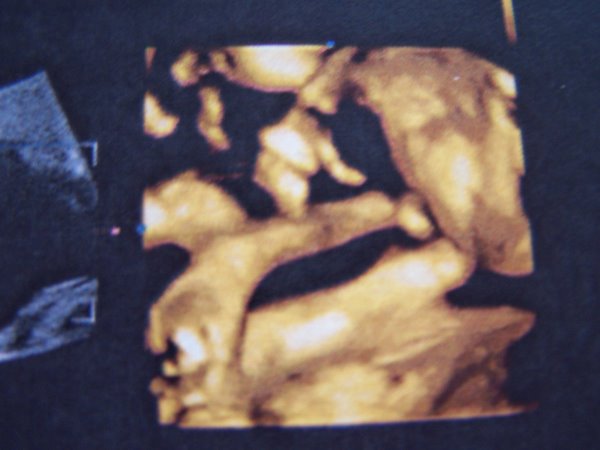

Szabim is mindig kisebb volt, mint Nati, 2 évesen is még 4 cm-rel alacsonyabb. Nem mindenki egyforma, az kb az első 12 hétre jellemző, utána már óriási eltérések lehetnek. Egy másik dolog pedig, hogy az uh amolyan saccra megy. Szabit születése előtt pár órával 2-2,5 kg-ra tippelték és jól beijeszettek. 2800-zal született, ami ugyan nem egy díjbírkózó, de teljesen ok.